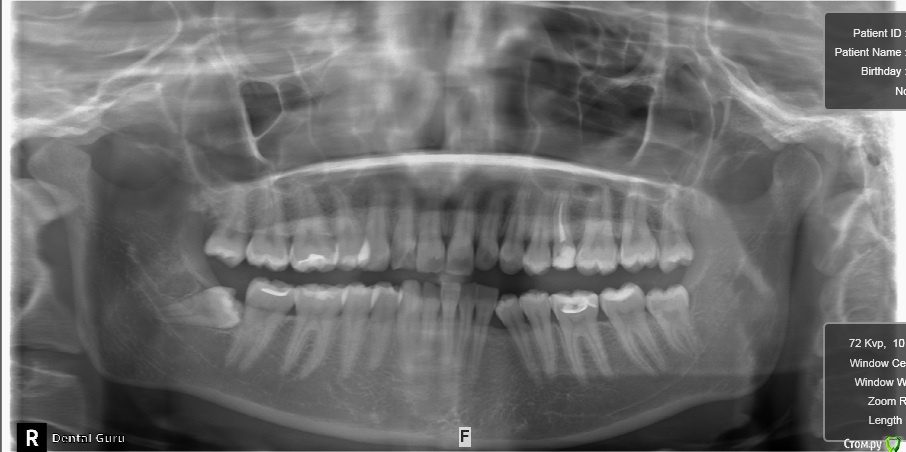

Здравстуйте! Мне 23 года.  У меня смещен центр верхней челюсти вправо и нижней влево. Больше беспокоит меня верх. На верхней челюсти, справа, отсутствует второй премоляр. На нижней клык слева. Премоляр мне в детстве удалили, он рос сверху зуба. Про нижний клык не помню. Проходила лечение не пластинке, не помню, к сожалению, почему. Очень хочу исправить эту ситуацию с зубами, но боюсь решиться, хочется получить гарантию от доктора, что все будет хорошо. Была на 3-х консультациях. На двух сказали что центр сместить нельзя. На одной доктор сказала, что нужно удалить сверху премоляр слева и снизу клык справа. Меня  интересует можно ли это исправить и каким методом, обязательно ли с удалением. Буду очень благодарна за помощь!!